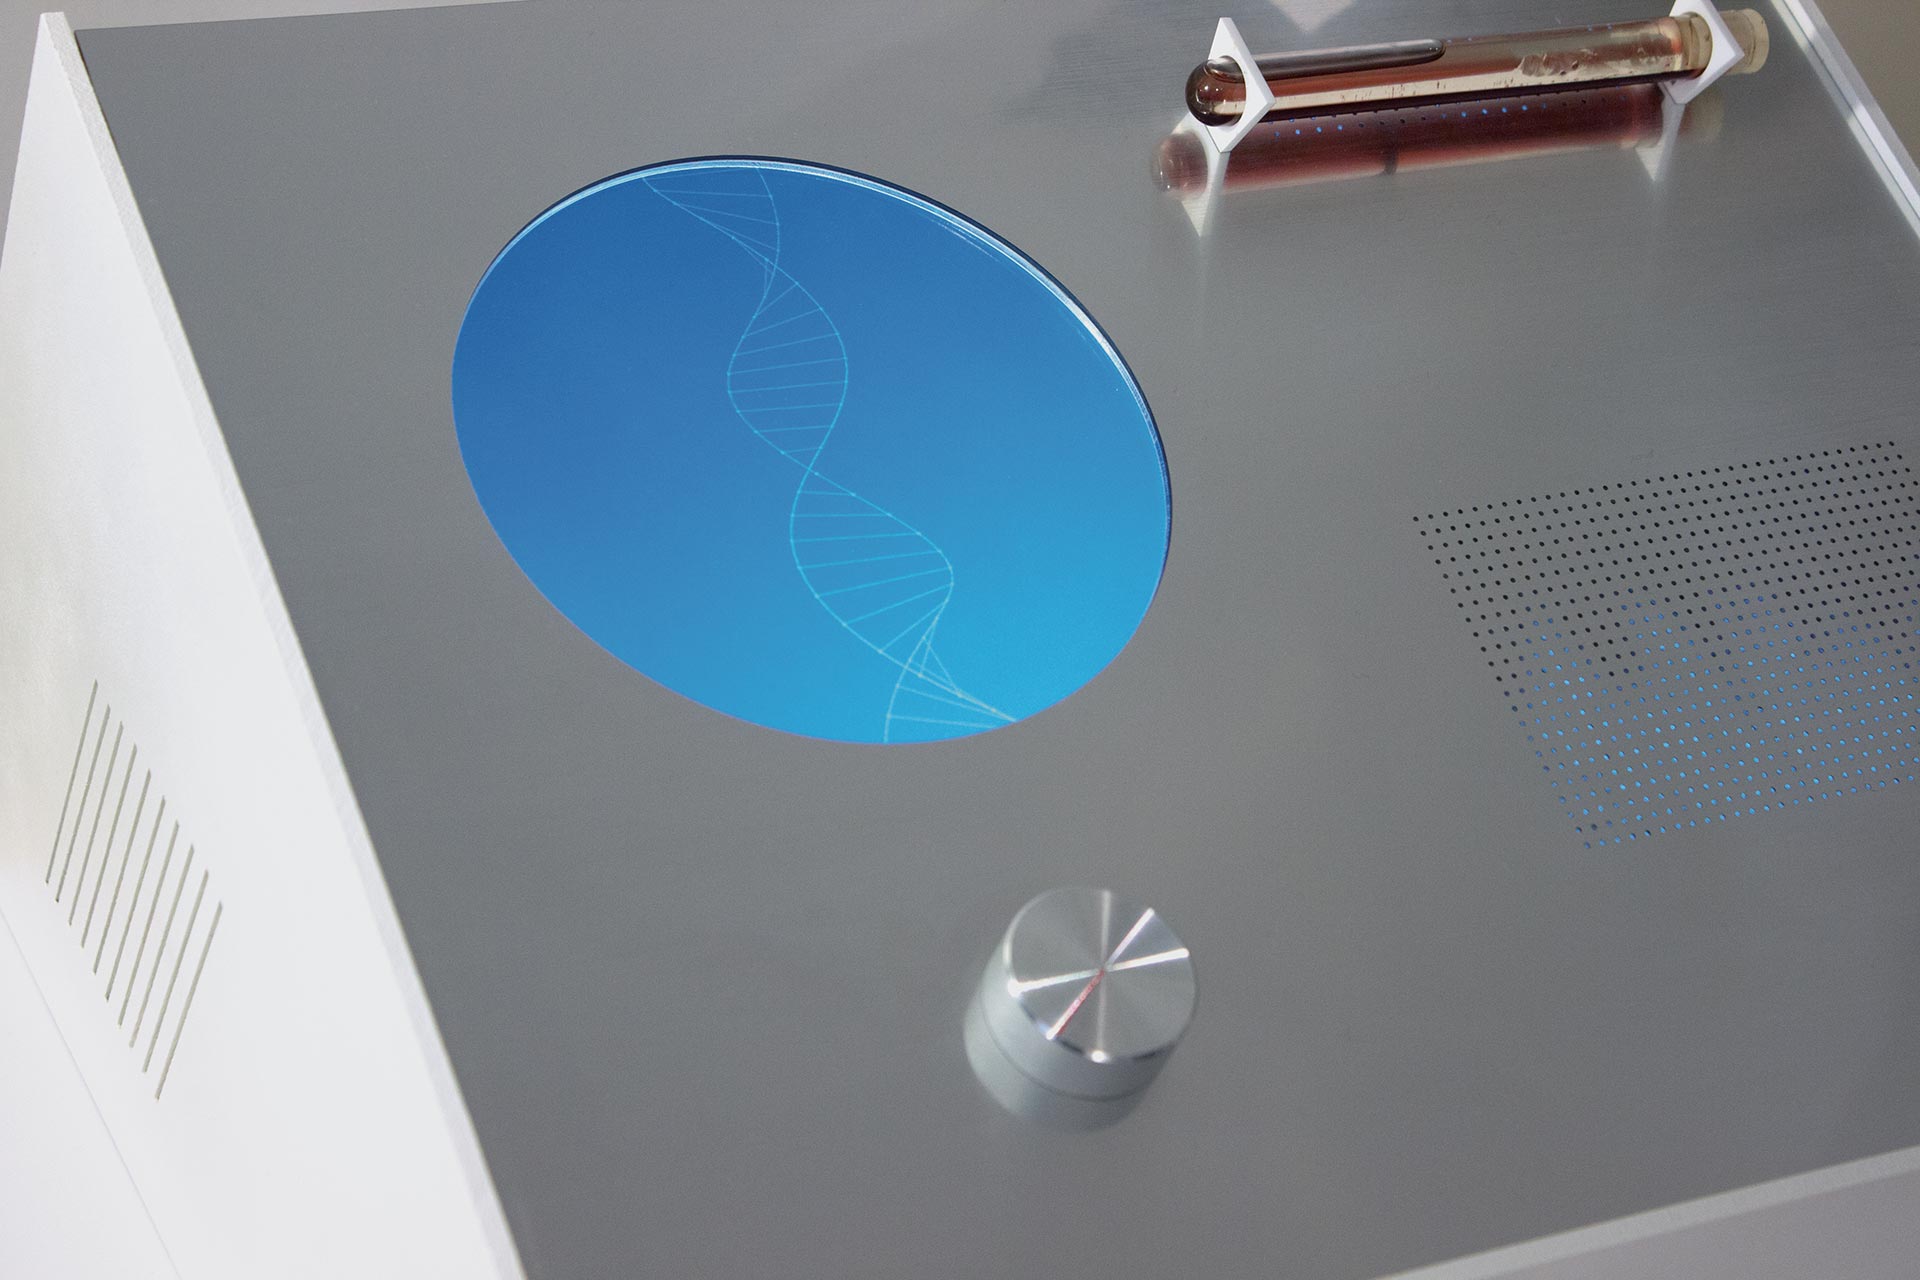

The Beauty of Oppositions

ID # 24661

Universität der Künste Berlin, DE

professors : Joachim Sauter, Jussi Angeslevä, Siegfried Zielinski

Stephan Sunder-Plassmann

contact :

www.stephansunderplassmann.com